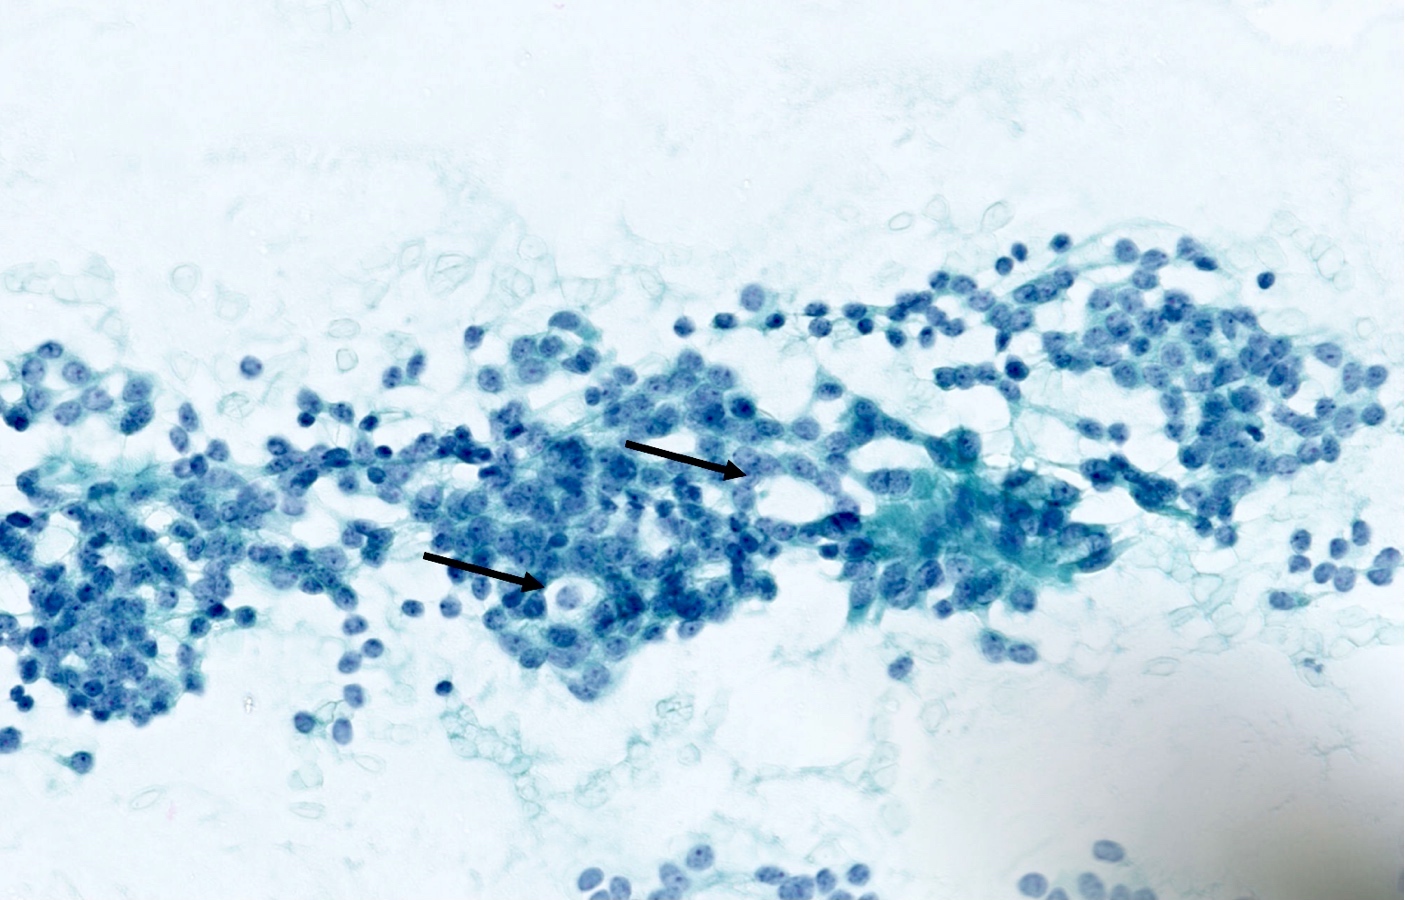

Cytology description

- Loosely cohesive groups and isolated cells sometimes around branching capillaries; rosette structures may be seen (Cibas: Cytology - Diagnostic Principles and Clinical Correlates, 4th Edition, 2014)

- Uniform population of small tumor cells with round / elongated or plasmacytoid shape

- Smooth nuclear outlines, uniform with salt and pepper chromatin and a small nucleolus; no or rare mitoses

- Scant granular cytoplasm

- Absence of molding, nuclear crush and necrosis

Cytology images